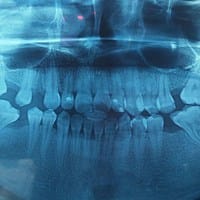

Es difícil dar diagnóstico así, se necesita radiografía para hacer una buena valoración.

Se necesita más exámenes, necesito radiografía del diente.